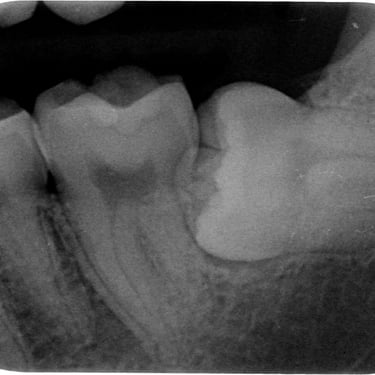

Quiste dentígero

Un quiste dentígero es un saco lleno de líquido que se forma alrededor de la corona de un diente no erupcionado.

Los pacientes pueden notar una hinchazón indolora en la mandíbula.

El tratamiento incluye la extirpación quirúrgica del quiste y, a veces, la extracción del diente involucrado.